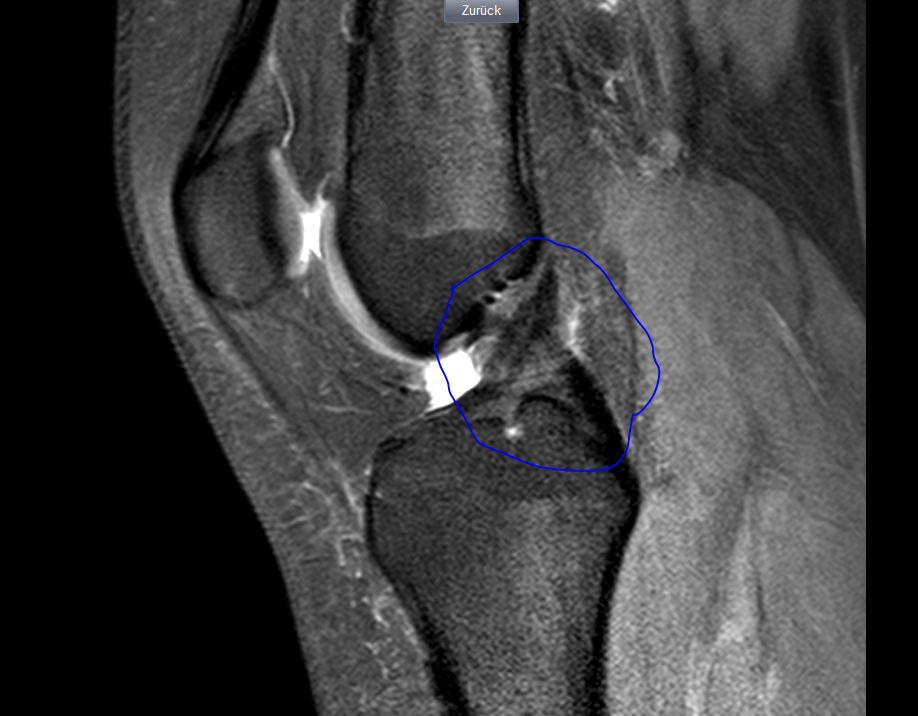

Die Kernspintomographie (Magnetresonanztomographie, MRT) eignet sich zur Darstellung verschiedener Organe und Strukturen im Körper. MRT-Bild einer Kniearthrose: Deutlich zu erkennen ist die durch den Knorpelabbau bedingte Verschmälerung des Gelenkspaltes in der medialen (inneren) Kniegelenkskammer. Finn de beste gratis arkivbildene om mrt.

MRT Bilder Kniegelenk und verschiedene Aussagen von Ärzten?